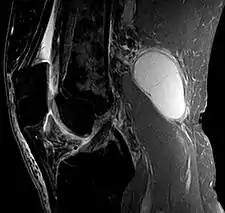

Baker's cyst on MRI, sagittal image